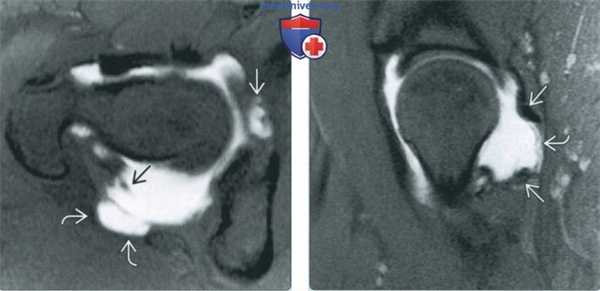

(Справа) Артроскопия, этот же пациент: отмечается, что суставная губа была восстановлена и прикреплена к вертлужной впадине швами в, удерживаемыми фиксаторами в кости. Неровность контура суставной губы все еще сохраняется. Следует отметить наличие глубокого дефекта суставного хряща, что является фактором неблагоприятного исхода после хирургической коррекции БВИ. (Слева) МР-артрография в режиме Т2ВИ FS, коронарный срез, пациент с нестабильностью тазобедренного сустава после артроскопии: определяется дефект в латеральном отделе суставной капсулы. Заметным, хотя и не специфическим признаком нестабильности является отек костного мозга.

(Справа) Артроскопия, фронтальная проекция, этот же пациент: выявляется крупный дефект суставной капсулы. Место осгеохондропластики подверглось заживлению. (Слева) МР-артрография в режиме Т1ВИ FS, аксиальный срез, пациенте нестабильностью тазобедренного сустава в послеоперационном периоде: визуализируется дефект переднего отдела суставной капсулы. Контур передней суставной губы неровный.

(Справа) МР-артрография в режиме PD FS, сагиттальный срез, этот же пациент: отмечается отсутствие передневерхней суставной губы после восстановления. Металлический артефакт - следствие операции. Контрастный препарат через дефект в суставной капсуле распространяется кпереди от сустава. Видна культя пересеченной подвздошно-бедренной связки. Остеохондропластический дефект ничем не примечателен. (Слева) МР-артрография в режиме PD FS, аксиальный срез, пациент с нестабильностью тазобедренного сустава после артроскопии: визуализируется дефект переднего отдела суставной капсулы. Контрастный препарат распространяется вокруг подвздошно-поясничной мышцы. Область остеохондропластики ничем не примечательна.

(Справа) МР-артрография в режиме Т1ВИ FS, сагиттальный срез, этот же пациент: здесь также выявляется дефект суставной капсулы. По сравнению с предоперационным исследованием отмечается отслоение хряща: контрастный препарат затекает между хрящом и костью. Дефект хряща подвергся хирургической обработке, суставная капсула была закрыта.